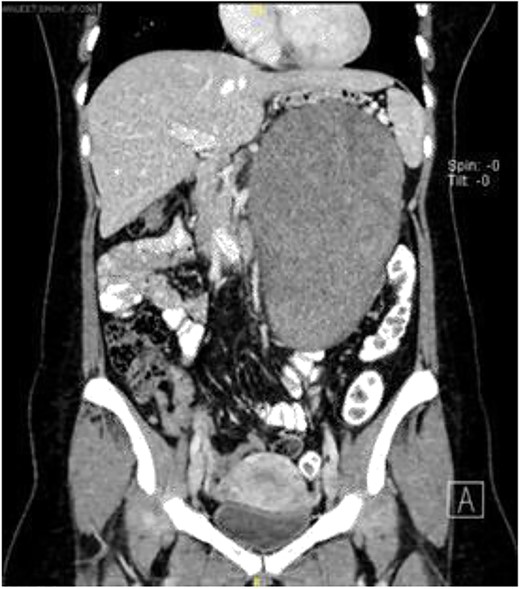

Computerized tomography scan demonstrated a large, well-defined lobulated heterogeneously enhancing solid cystic mass sized 10.7 cm × 12.7 cm × 22.2 cm. The mass displaced the pancreas anteriorly, and it compressed onto the splenic vein with collateral vessels seen, draining into the portal vein. Posteriorly, the lesion displaced the left kidney posteriorly and compressed onto the left adrenal gland superiorly. The remaining structures were unaffected (Fig. 1).